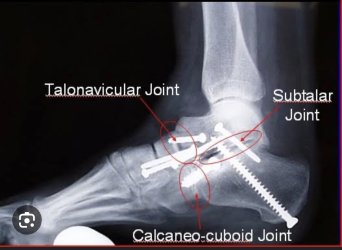

If really bad then depending on the actual joints involved a fusion procedure where they remove the joint surfaces in question and fuse the bones

That fusion is a minor one involving the big toe joint. Quite common for arthritis of that joint

The foot one is much more invasive